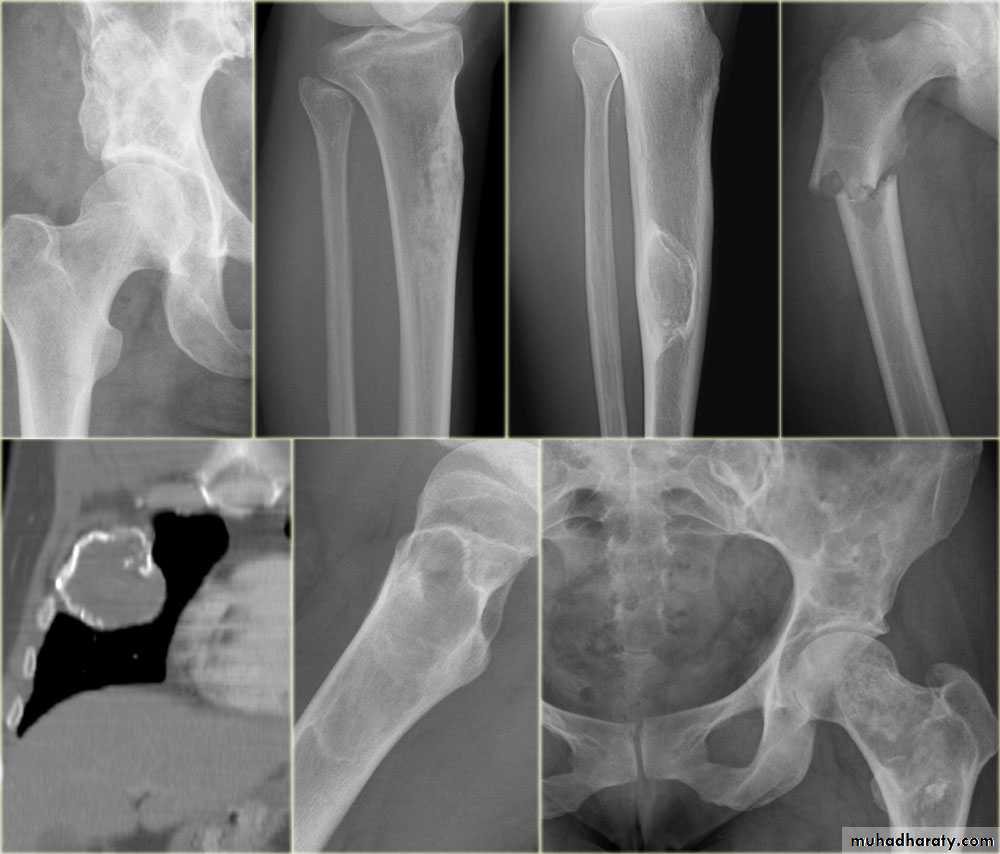

the initial radiological decision is usually to try &decide whether the solitary lesion is benign or its aggressive by looking for the following features on plain radiographs & CT :

1.Zone of transition

2.The adjacent cortex

3.Expansion

4.Periosteal reaction

the causes of localized peiosteal reactions adjacent to a lytic or sclerotic lesions are :

.Osteomyelitis.Malignant bone tumour , particularly Ewing sarcoma & osteosarcoma

.Occasionally metastasis , particularly neuroblastoma

.Langerhans histiocytosis

.Trauma

5. Calcific densities within the lesion

6. Soft tissue swelling

7.Site:The site of a lesion is most important as certain lesions tend to occur at certain sites.Bone tumours